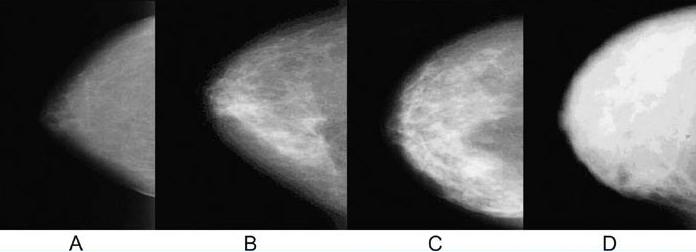

치밀유방(Dense Breast) VS 지방화유방(Fatty Breast)

유방은 크게 지방조직과 유선조직으로 이루어져 있습니다. 이 두 조직의 구성 비율에 따라 치밀유방과 지방화 유방으로 나뉘는데 이는 연령과 분만유무 등에 따라서도 변화를 보입니다.

유방촬영술 상에서 지방조직은 어두운 음영으로 나타나게 되고 유선조직은 하얗게 나타나는데 위 사진에서 보면 왼쪽 A는 하얗게 보이는 유선조직의 분포가 적으며 대체적으로 어두운 음영인 지방조직의 분포가 많은 지방화유방이며 D로 갈수록 유선조직이 풍부해 지며 하얗게 보이는 부분이 넓게 퍼져있는 즉, 유선조직이 조밀하게 뭉쳐있는 분포인 치밀유방이라고 합니다.

동양인들은 서양인들에 비해 유방이 작고 유선조직이 풍부하게 발달되어 치밀유방인 경우가 많은데 이런 경우에는 유선조직에 병변들이 가려 발견이 어려운 경우가 많으므로 유방초음파 검사를 받아보시는 것이 좋습니다.